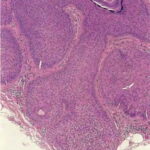

Middle-aged and elderly individuals are commonly

affected. Pilar sheath acanthoma is characterized by a small (5 to 10 mm in diameter), solitary, skin-colored papule situated on the head and neck, particularly around the upper lip. A central, occasionally keratin plugged pore is often present. Histologically, there is a crateriform depression in the epidermis representing a widely dilated, keratin-filled infundibulum or closely set infundibula contiguous at the base with numerous epithelial lobules of pink keratinocytes. The epithelial lobules radiate into the dermis, sometimes with involvement of the subcutis. They are surrounded by a narrow rim of fibrous tissue. The epithelium shows similar features to those of the isthmus of a normal hair follicle. Small infundibulocystic structures, tubular structures, and foci of sebaceous differentiation (ducts or sebaceous lobules) are variably observed in individual cases. Treatment is surgical excision